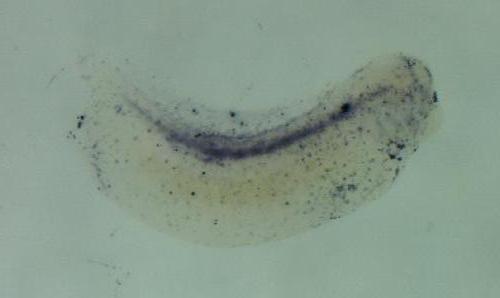

f13a1

coagulation factor XIII, A1 polypeptide

The f13a1 gene encodes a transglutaminase enzyme which functions in blood coagulation by cross-linking fibrin clots to stabilize them; this activity is present in skin mucus where it contributes to wou...[+]